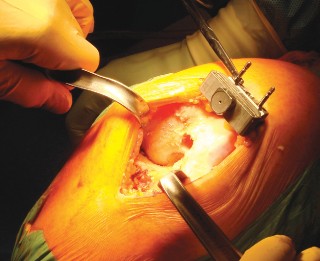

Digital Templating and Implant Selection

Meticulous preoperative templating is the blueprint for a successful TKA. Utilizing digital templating software on calibrated radiographs allows the surgeon to anticipate the required component sizes, determine the optimal level of bony resection, and identify potential anatomical anomalies. On the AP radiograph, the femoral component size is estimated by matching the mediolateral width of the implant to the distal femur, avoiding overhang which can cause soft tissue irritation. The tibial component is sized to maximize cortical coverage without impinging on the collateral ligaments.

On the lateral radiograph, templating is critical for preventing anterior femoral notching, a technical error that significantly increases the risk of postoperative periprosthetic supracondylar femur fractures. The size of the femoral component is chosen to restore the anteroposterior dimension of the native femur, ensuring the anterior flange sits flush with the anterior cortex while the posterior condyles restore the flexion gap. The expected thickness of the polyethylene insert is also estimated, aiming for a composite tibial construct that restores the native joint line elevation.

The distal femoral resection is typically performed first, utilizing an intramedullary alignment guide. The entry hole is made just anterior to the origin of the PCL. The valgus angle of the cutting block is set based on preoperative templating (usually 5 to 7 degrees) to restore a neutral mechanical axis. The distal cut removes approximately 9 mm of bone from the most prominent condyle, corresponding to the thickness of the femoral component.

Next, the proximal tibial resection is executed, almost exclusively using an extramedullary alignment guide. The guide is aligned with the medial third of the tibial tubercle proximally and the center of the talus distally. The cutting block is set to resect 8 to 10 mm of bone from the unaffected compartment, incorporating a 3 to 5-degree posterior slope. This cut must be strictly orthogonal to the mechanical axis of the tibia in the coronal plane.

Femoral sizing and rotation are then determined. Proper femoral rotation is paramount for patellofemoral tracking and flexion gap symmetry. The rotation is typically set at 3 degrees of external rotation relative to the posterior condylar axis (PCA), or parallel to the surgical transepicondylar axis (TEA) and perpendicular to Whiteside's line (the AP axis of the trochlea). Once rotation is established, the anterior, posterior, and chamfer cuts are made using a 4-in-1 cutting block.